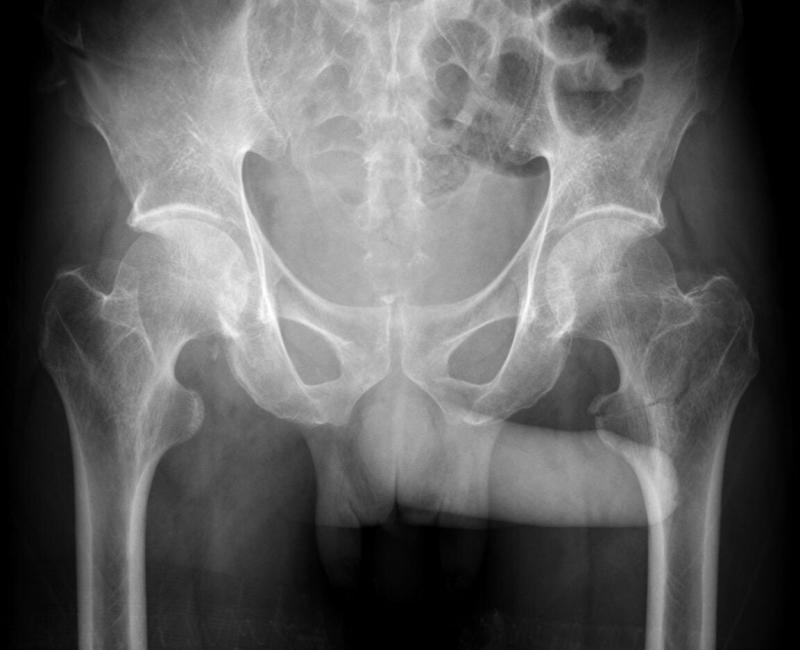

골반 엑스레이 찍는데

그 상태로 엑스레이 찍고 다 되셨다고 나가라 해서 나왔는데

엑스레이에 발기된것도 나오나요?? 하.....